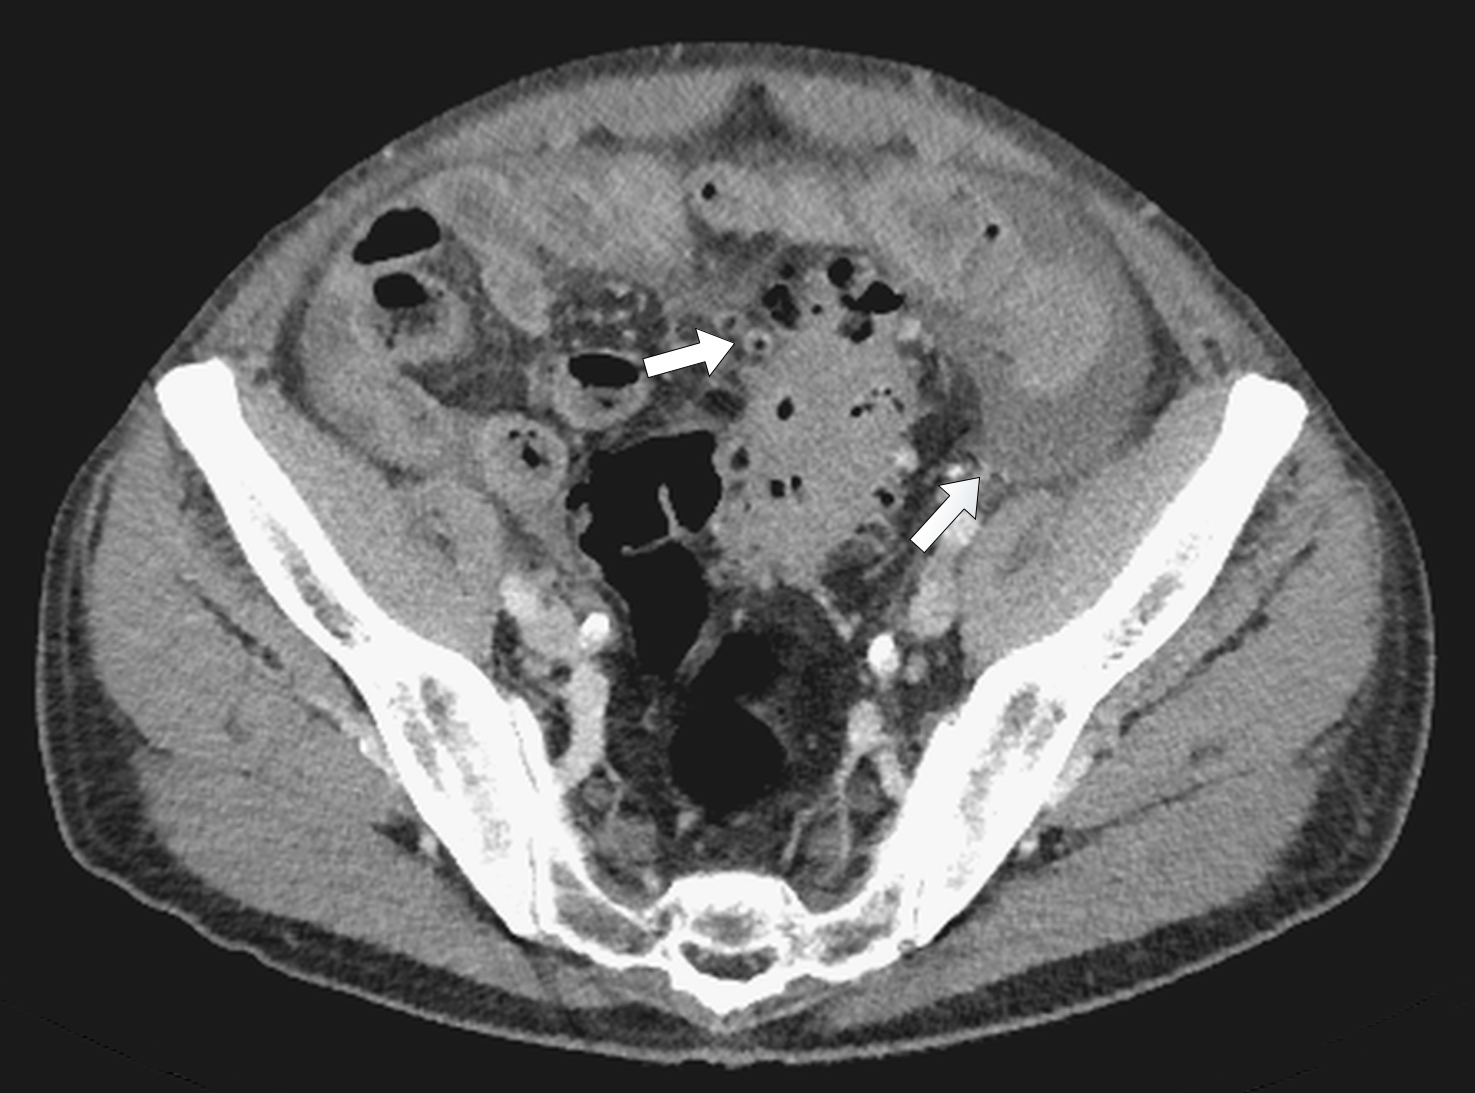

showed considerable free fluid, free air and a thickened wall of the sigma with multiple diverticula imposing as a pseudotumor without signs of an acute inflammation (Figure 2). This rose the suspicion of a traumatic sigma perforation. The left inguinal canal was fluid-filled with free air present (Figure 3). Because of the absence of an intensive care unit the patient was transported to a tertiary referral hospital for an urgent explorative laparotomy. The inspection showed a feculent 4-quadrant peritonitis with a perforation of the small bowel 50cm proximal to the ileocecal valve. The perforated small bowel was resected as a segment. A side-to-side ileostomy was formed. The sigma was indurated on palpation and suspicious of a colon cancer. In the intraoperative rectoscopy the tumor could not be reached. The inguinal canal was filled with stool and a lavage was performed together with the whole abdomen. A drainage was placed and the abdomen closed temporary with a negative-wound-pressure therapy (NWPT) system. The preoperatively started intravenous antibiotic treatment with imipenem was continued. On the first postoperative day, a rectosigmoidoscopy was unable to pass the stenosis in the sigma. A repeat CT of the abdomen with rectal and intravenous contrast showed wall thickening of the sigma with perifocal lymphadenopathy (Figure 4). In the 2nd look laparotomy 48 hours after the initial operation an anterior resection with complete mesocolic excision and partial mesorectal excision was performed because a malignant disease could not be excluded. A descendorectostomy was performed and the side-to-side ileostomy was reversed into a protective splitstoma. Again, the inguinal hernia was not touched due to the contamination. The NWPT was continued and after two NWPT changes primary fascial closure was achieved eleven days later. The histopathology showed a covered perforation of a sigma diverticulitis with inflamed pseudotumor without signs of malignancy. 22 days after the tennis accident the patient was discharged for rehabilitation. One month later he is in a good health condition and is waiting for the reversal of the stoma and definitive treatment of the inguinal hernia.